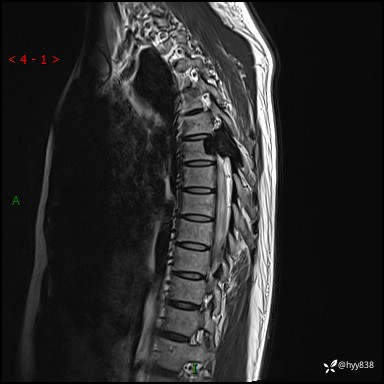

胸椎MRI平扫(sag T1WI+T2WI)